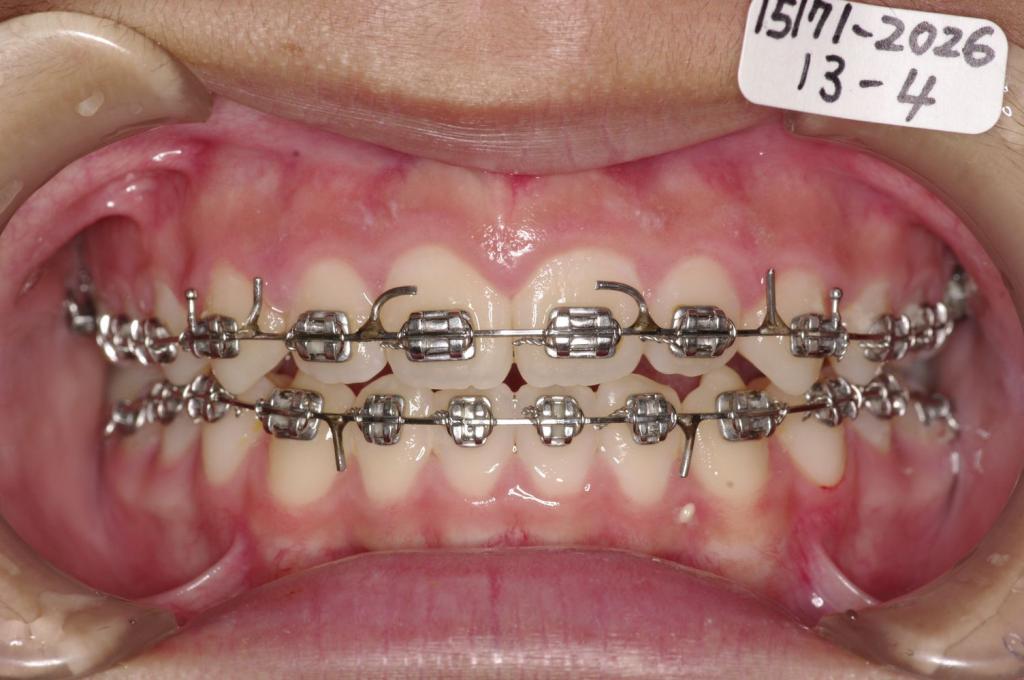

治療後

前歯、出っ歯・開咬の矯正治療後口内写真NO.1105